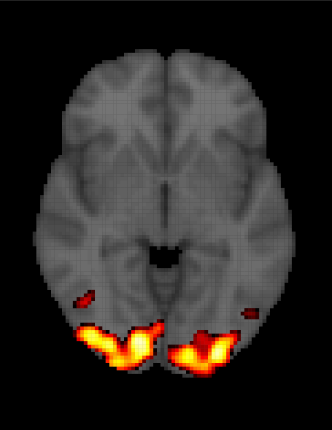

for and , where is the number of voxels in the fMRI array and is the number of observations in each time series. and are the observed (obtained from the scanner) and expected ( obtained from equation 1.2) BOLD response, respectively. Then the parameter will inform about the time series voxels () that match with expected BOLD response . In this type of modeling, a key feature of any fMRI dataset is totally ignored: the spatio-temporal relationships. Thus, in the model 1.3, independent observations inside each voxel (temporal independence) are assumed, as is independence among voxels (spatial independence), both unrealistic suppositions. One of the main consequences of performing this type of analysis is getting incorrect inferences about the parameter and a high rate of false positives, in other words, identifying a brain activation when it really does not exist. A common practice to fix this problem is to use some sort of corrections, like the Bonferroni correction or spatial extent methods (Worsley \BBA Friston (\APACyear1995)), among others. For instance, in figure 1.6 we can see an example of an activation of the visual cortex. In the left panel, the inference is performed without any type of correction and in the right panel, a Bonferroni correction is used. From this example, we might think that this kind of method could help solve the problem of detecting a false activation pattern. However, Eklund \BOthers. (\APACyear2012) and Eklund \BOthers. (\APACyear2016) evaluate the most common software packages for fMRI analysis using real data, and they find that in general, those correction methods do not work very well. Specifically, they use resting-state data and a total of 3 million random task group analyses to compute empirical familywise error rates. For a nominal familywise error rate of 5%, parametric statistical methods are shown to be conservative for voxelwise inference (e.g., using the Bonferroni method) and invalid for clusterwise inference (e.g., using spatial extent methods).

| (a) | (b) |

|---|---|

![]() |